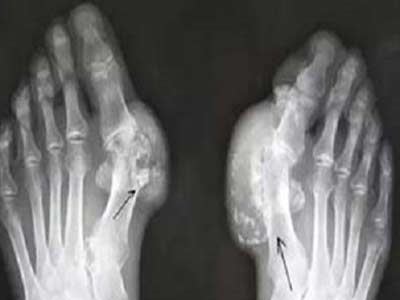

1、出现痛风石。痛风石的形成与痛风的病程长短、体内血尿酸高低有很大关系,病程越长,形成痛风石的几率就越大,高尿酸血症持续时间越长,越易形成痛风石。

2、痛风慢性关节炎。这是痛风较易引起的疾病之一,由于痛风石在骨关节周围组织沉积而引起组织的炎症反应性损伤,久而久之就会形成慢性关节炎,后期治疗起来更复杂,费用也会更高。